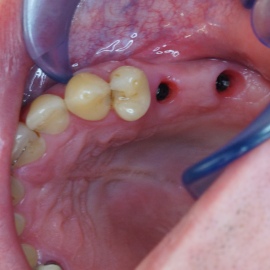

Pacjentka lat 72, od kilkudziesięciu lat chorująca na cukrzyce I typu, obecnie od 10 lat na pompie insulinowej. Profesor medycyny, siostrzenica pacjentki prowadzi swoją ciocię diabetologicznie, pacjentka świadoma zagrożeń przy zabiegach regeneracji kości i implantacji w takim ogólnym stanie zdrowia. Po rekonstrukcji tkanek miękkich i kości osadzono dwa implanty o średnicy 5,0 mm. Na zdjęciu śródzabiegowym widać zadowalające wyniki rekonstrukcji tkanki kostnej. Po upływie kilku miesięcy wykonano nadbudowę protetyczną.